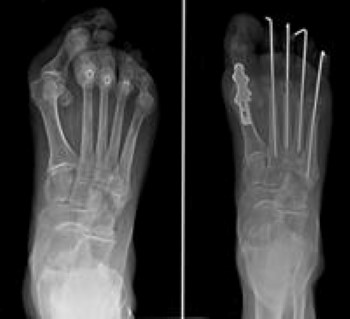

- If the RA has progressed and the lesser toes (2 through 5) have dislocated, a complex operation to minimize the pain and restore the shape of the foot may be recommended. The operation involves fusion of the big toe and removing a portion of bone of each of the metatarsals. This surgery removes the prominent bone on the bottom of the foot that is a source of the pain and allows the toes to re-align into a better position.

- If the deformity has not progressed as far or is relatively mild, the lesser toe metatarsals can be preserved or shortened to allow the toes to resume their position within the joints. This is not always possible, however, and the joint may have to be removed.

To fix the bend in the toes themselves, the surgeon may suggest cutting a tendon or removing a small portion of bone of the toes to allow them to straighten. Pins that stick out of the foot are temporarily required and will be removed in the office after healing takes place.

There are some implants available that can be buried within the toes, which avoid the need for pins sticking out of the foot. These implants may not work if the bone is soft, or if significant destruction of the joints has occurred, and treatment of complications can be more challenging with implanted hardware in the smaller toes.